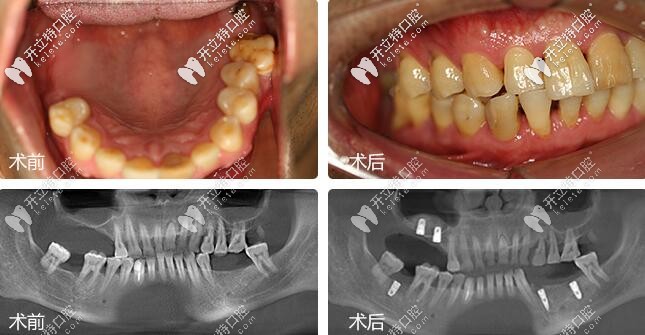

鄭蒼尚院長微創(chuàng)種植牙案例▼